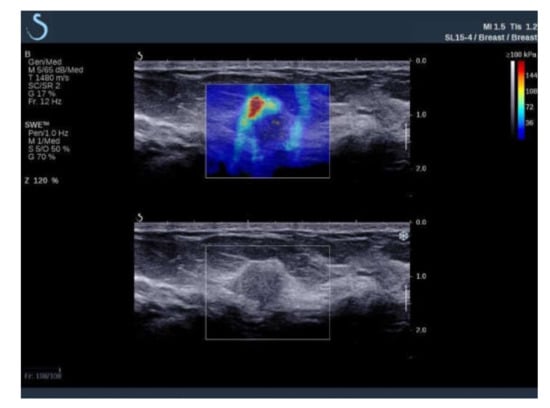

Elastic Modulus and Elasticity Ratio of Malignant Breast Lesions with Shear Wave Ultrasound Elastography: Variations with Different Region of Interest and Lesion Size